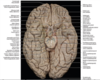

Key gyri on superior view of frontal cortex

Superior frontal gyrus

Middle frontal gyrus

Inferior frontal gyrus

Precentral gyrus

Key sulci on superior view of frontal lobe

Superior frontal sulcus

Inferior frontal sulcus

Precentral sulcus